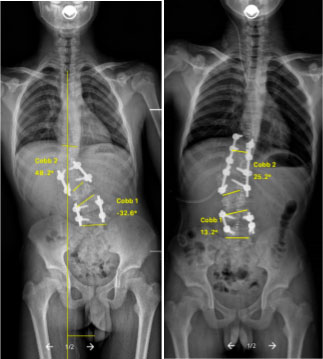

术前 术后

为了保证孩子的生活质量、腰椎的活动度且又要达到良好的矫形效果,这是一个巨大挑战及考验。手术方案设计为拆除原有的两处脊柱内固定,切除致病的“恶性”半椎体,充分松解,再后路O臂导航下进行椎弓根螺钉固定矫形,对两处内固定中间地带,不进行融合、固定。

术后,在脊柱外科快速康复外科治疗团队的努力下,小男孩在术后第2日可自行下地行走,逐步恢复正常生活,并积极进行康复锻炼。